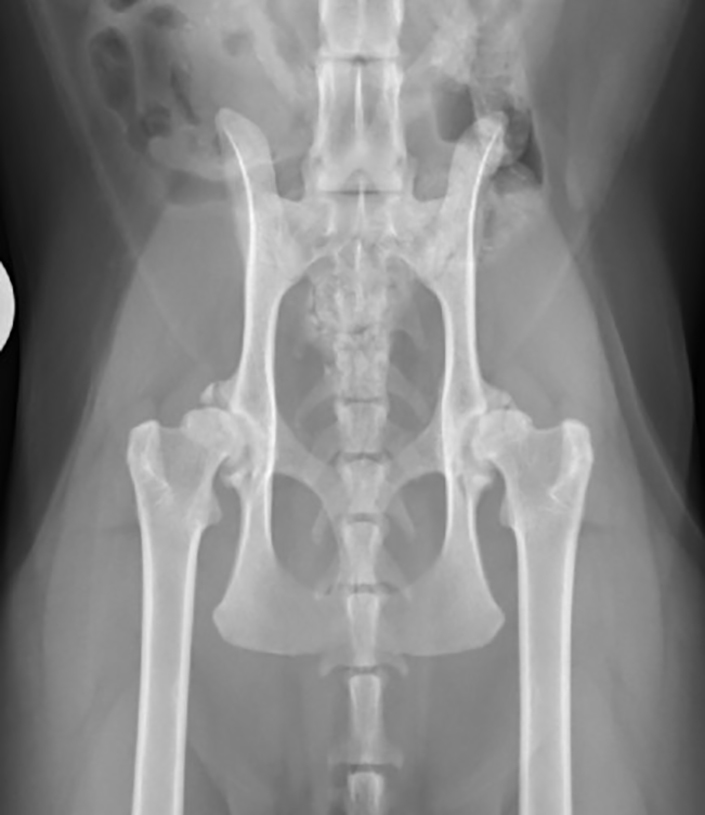

Figure 3. Cataleyia, an 11-year-old, female, spayed domestic shorthair, presenting for intermittent shifting thoracic limb lameness of two months duration.

Cataleyia, an 11-year-old female, spayed domestic shorthair, presented for intermittent shifting thoracic limb lameness of two months’ duration (Figure 3). She was an indoor-only cat in a single cat household. The owner reported no inciting events that may have caused the lameness. She was otherwise reported to be doing very well at home, with a normal appetite and no evidence of vomiting, diarrhoea, coughing or sneezing. The FMPI clinical metrology instrument was completed and a result of 56% indicated moderate impairment.